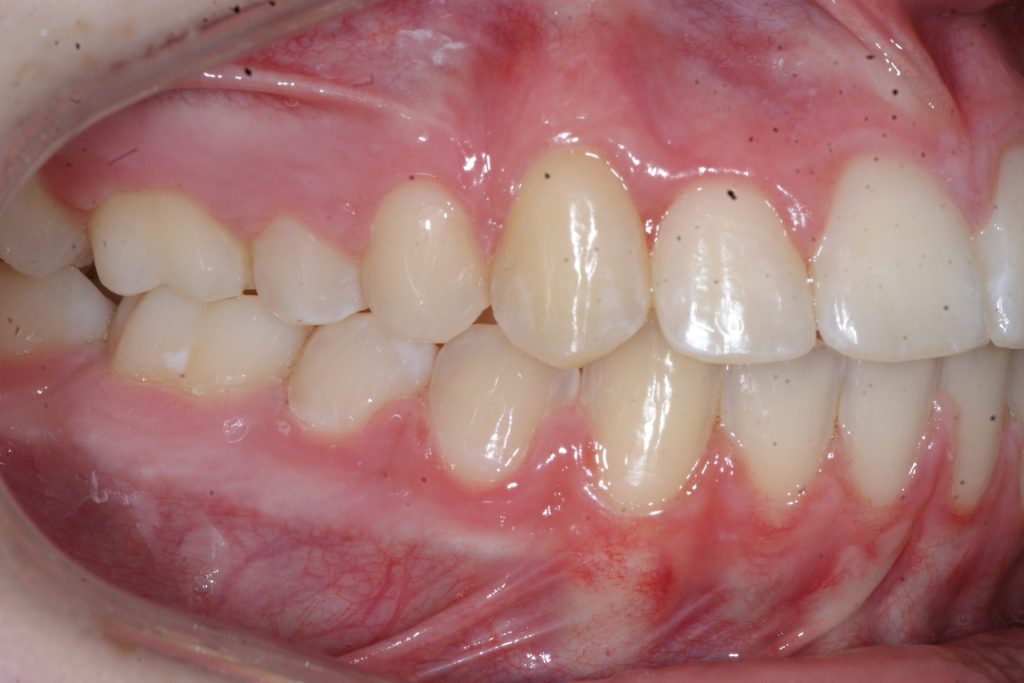

Correction d’une malocclusion de type Classe II subdivision avec canine ectopique (#14).  Des appareils fixes (boîtiers) et l’extraction d’une prémolaire (#15) furent nécessaires pour améliorer ce sourire.  Traitement chez une adolescente, réalisé en 21 mois.